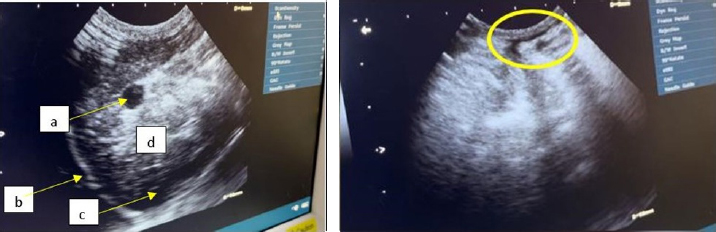

The findings of USG performed in the dorsal recumbent position on the thoracic and abdominal regions revealed the existence of fluid accumulation in the peritoneal cavity (Fig. 4).

The abdominal cavity examination conducted through USG revealed certain structures appearing anechoic on the sonogram, indicating the presence of ascitic fluid in the abdominal cavity (Prajapati et al., 2022).

The findings from the ultrasound assessment revealed that the cardiac organ exhibited a normal structure (Fig. 5). The inability of researchers to utilize color flow Doppler imaging, a modality that permits direct visualization of blood flow velocity within the heart and related blood vessels, and consequent description of turbulent blood flow patterns, has precluded observation of blood flow in the heart of the Hiro cat.

Fig. 4. The abdominal region of Hiro, a feline specimen, displays the presence of ascites as evidenced by medical imaging using USG.

Fig. 5. Ultrasound results of cat Hiro’s heart structure, (left: long axis, right: short axis) right parasternal view position.

The X-ray findings reveal a change in opacity in a section of the abdominal cavity, indicating an increase in radiopacity and the presence of ascites, or fluid buildup. Ultrasound imaging of the same area reveals anechoic regions between organs, which is a sign of fluid accumulation (Prajapati et al., 2022). Ascites are a symptomatic condition that occurs when fluid, both transudate and exudate, leaks into the space between the peritoneum and visceral layer of the abdominal cavity (Tilley et al., 2021). This is often a result of congestive heart failure or impaired venous flow and may cause cats to experience lethargy, abdominal distension, discomfort upon palpation, anorexia, vomiting, weight gain, scrotal or prepuce edema, and pain while lying down. Hypoalbuminemia, or low levels of albumin in the blood, is a contributing factor to ascites, as it reduces plasma osmotic pressure and increases vascular permeability, leading to fluid leakage from blood vessels into the abdominal cavity (Restijono et al., 2020).